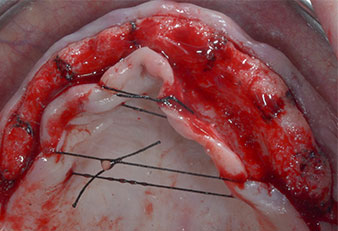

Tres años después, llegó el momento de colocar una prótesis del mismo tipo en el maxilar superior. Basándose en una planificación mediante tomografía computarizada de haz cónico (CBCT, por sus siglas en inglés), se evitó la necesidad de realizar una elevación del seno utilizando implantes cortos, mientras que una plantilla quirúrgica sirvió para transferir las posiciones planificadas al borde alveolar (figuras 1 y 2).

Para marcar las posiciones del implante y realizar la preparación piloto, se utilizó un inserto piezoeléctrico (Piezomed I1) con revestimiento de diamante y forma de llama (figura 3). Se tomaron precauciones para realizar movimientos hacia arriba y hacia abajo, con una potencia reducida, una irrigación completa y una baja presión (por debajo de 300 g). A continuación, se aplicó un inserto piloto (Piezomed I2A/I2P) para aumentar el diámetro inicial de 2 mm de los sitios de implante (figura 4), seguido de un inserto de 3 mm (Fig. 5).